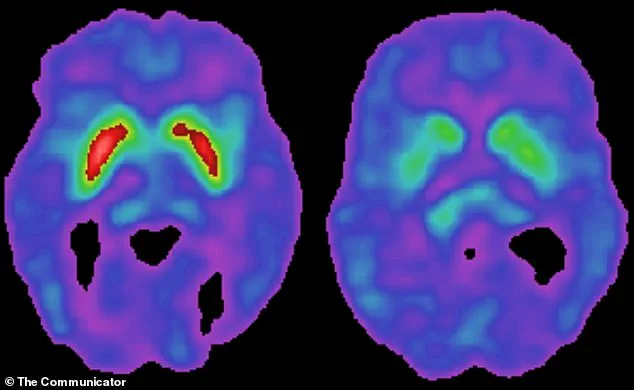

Parkinson’s disease is characterized by the gradual degeneration of dopamine-producing neurons in the brain, leading to symptoms such as tremors, stiffness, and difficulty with movement.

Brain tissue from 24 deceased individuals—10 with Parkinson’s and 14 without—further confirmed the virus’s association with the disease, with HPgV detected exclusively in Parkinson’s brains.

When the brain detects a virus, it initiates an inflammatory response to combat the threat.

However, chronic or excessive inflammation can inadvertently damage neurons, including the dopamine-producing cells that are central to Parkinson’s pathology.

This dual-edged effect of the immune system may explain how HPgV, even in its dormant state, could contribute to the disease’s progression over time.